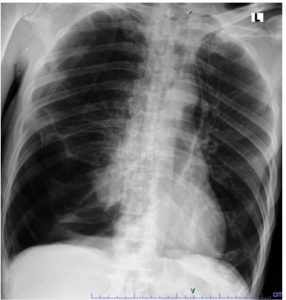

A 69-year-old male patient presented to the emergency department of Dr. Soetomo General Hospital with complaints of cough and shortness of breath that had started 30 min earlier. At the time of admission, the patient was alert and febrile with a temperature of 37.9 °C. His blood pressure was 129/70 mmHg, heart rate was 120 beats/min, and respiratory rate 28 times/min. Oxygen saturation reached 98% while receiving oxygen through a non-rebreathing mask at a flow rate of 10 L/min; history revealed that the patient had experienced similar symptoms two weeks prior and was diagnosed with spontaneous pneumothorax. The patient was then suspected of having pulmonary tuberculosis, especially considering that tuberculosis is endemic to Indonesia. The patient immediately underwent needle thoracentesis, followed by a GeneXpert® MTB/RIF Ultra test on a sputum specimen, which yielded negative results. The patient also underwent chest tube placement with active suction during the previous hospitalization period. After several days with a chest tube in place, the patient underwent a bullectomy and wedge resection using Video-Assisted Thoracoscopic Surgery (VATS). Upon showing improvement, the patient was discharged in a stable condition, with no shortness of breath, occasional coughing, good oral intake, and oxygen saturation levels of 96-98% on room air. However, the patient returned to the emergency room one day after discharge with the same complaints, namely sudden onset of cough and shortness of breath. Asymmetrical chest wall movement was noted, with the right-side lagging, accompanied by diminished vesicular breath sounds on the right side. Chest radiography revealed signs of pneumonia and right-sided pneumothorax (Figure 1).